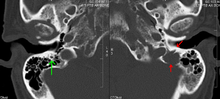

The work-up of suspected multiple myeloma includes a skeletal survey. This is a series of X-rays of the skull, axial skeleton and proximal long bones. Myeloma activity sometimes appear as "lytic lesions" (with local disappearance of normal bone due to resorption), and on the skull X-ray as "punched-out lesions" (pepper pot skull). Magnetic resonance imaging (MRI) is more sensitive than simple X-ray in the detection of lytic lesions, and may supersede skeletal survey, especially when vertebral disease is suspected. Occasionally a CT scan is performed to measure the size of soft tissue plasmacytomas. Bone scans are typically not of any additional value in the workup of myeloma patients (no new bone formation; lytic lesions not well visualized on bone scan).